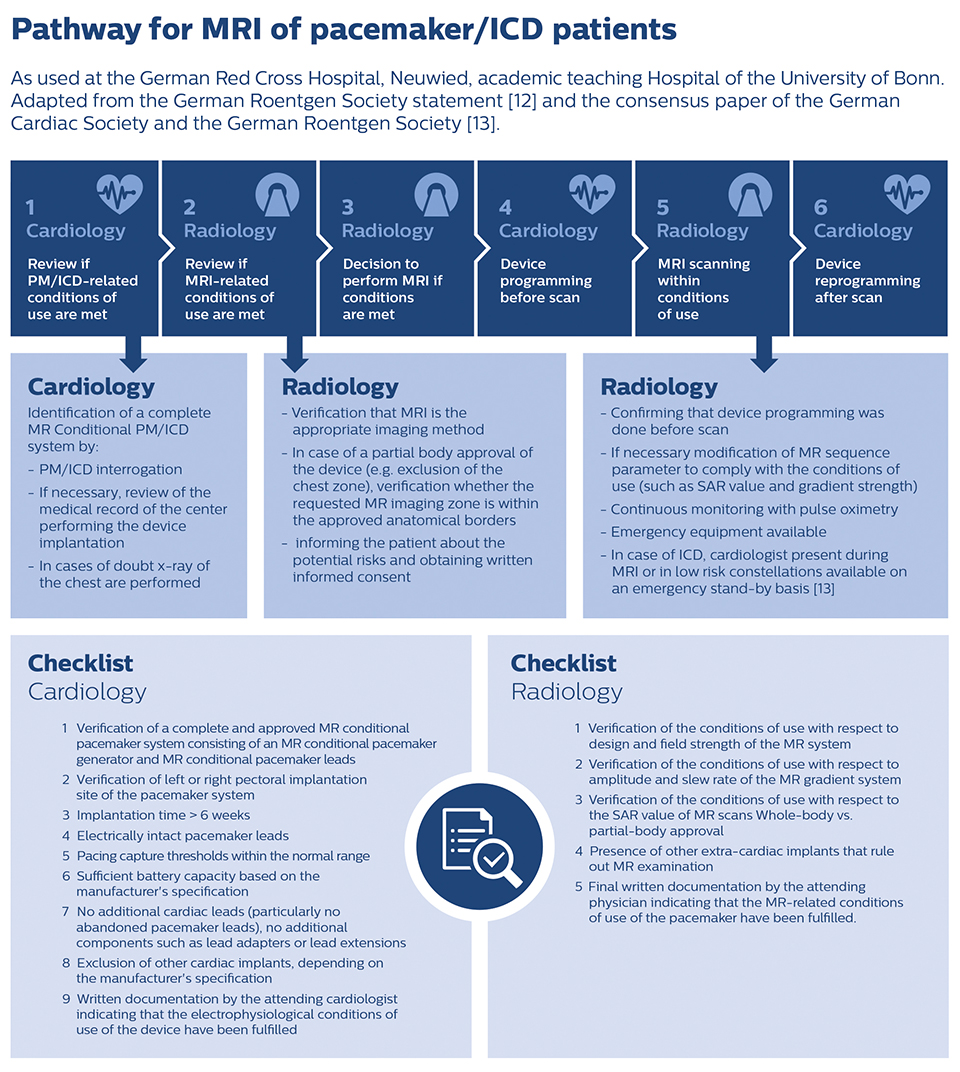

“We are using a dedicated pathway with an established cooperation with the cardiology department and are scanning about 250 to 300 pacemaker and ICD patients a year. So, for us it’s a quite familiar procedure which is fully integrated in the clinical workflow.”

When a patient with an MR Conditional active cardiac implant presents, the exact brand and type of the implanted device must first be determined. If the device is MR Conditional, then the next step is to retrieve the implant’s MR conditions that are specified by the implant manufacturer [9-10], for instance from the implant manufacturer’s documentation or website. Just before the MRI scan the implanted device is programmed to safe mode in the cardiology department and it is reprogrammed again after the MR exam. All scan sequences of the MRI exam must to be set up to stay within the limits and conditions specified by the implant vendor.

We have a process in place that includes electrophysiologists, who are experts in these devices, and imaging physicians, who are the experts in imaging,” says Dr. Patel. “Together they have set up a protocol and infrastructure so that the device can be interrogated before and after the MRI and it can be reprogrammed, as necessary, before and after. During the MRI scan, an ACLS (Advanced Cardiovascular Life Support) certified person with some expertise in device programming needs to be present to monitor the patient.” “The screening procedure for patients with cardiac implants can differ between sites,” says Dr. Shellock. “At many sites in the USA, the MRI technologist or radiographer is responsible for screening the patient, identifying an implant and then also looking at the information to determine what the MR conditions are for that particular implant or device. Technologists have the experience and are trained in MRI safety. There may be other MRI safety trained individuals, including imaging nurses, MRI technologist aides, or assistants, who have been appropriately educated and trained enough to handle screening procedures as well.”

A well-designed pathway benefits an efficient process

Jürg Schwitter, MD, cardiologist at the University Hospital of Lausanne, Switzerland explains that a well-designed patient trajectory is an essential element of providing an MRI service for patients with MR Conditional cardiac implants. “We established a pathway that we have been using for two or three years now. It is particularly important to control the workflow before the patient enters the MR suite. Our pathway helps us avoid waiting time at the machine and makes the technologists feel comfortable. As we do a lot of cardiac MR in the same unit, there is always a cardiologist around that they can consult. I think it's also important to emphasize the cost-effectiveness of our pathway: we manage to have almost no loss of machine time, when scanning pacemaker patients or ICD patients.”

Switching the MR Conditional device to scan mode

Dr. Schwitter’s institute in Switzerland schedules an appointment for the patient at the outpatient cardiology department 30 or 45 minutes before the MRI scan. “The patient goes to cardiology to switch the pacemaker to MR scan mode. After we performed the MRI exam, we send the patient back to cardiology for activating the pacemaker program again.” “There is a form that accompanies the patient, which the cardiologist signs at after activating the safe scan mode, and the technologist signs when the scan is done without any problems. Then the patient goes back to cardiology, the MRI-safe mode is switched off, and the cardiologist signs again and sends the form back to our department. In this way we know that everything was okay.” MRI of patients with an MR Conditional implant has become a routine procedure at Dr. Schwitter’s institute. “We do this quite often, several times per week. During the two to three years we have now used this procedure, there was not a single complication[11].”

Getting started involves three things

“In Germany information and education on performing MRI of patients with active cardiac devices is available to those who look for it [12,13]. The joint consensus paper of the German Roentgen Society and the German Cardiac Society provides physical and electrophysiological background information and specific recommendations for the management of patients with cardiac devices, outlining the responsibilities of radiology and cardiology regarding patient education, indications, monitoring and device reprogramming,” says Dr. Sommer. “In the end, I think three things are important for safe and successful MR imaging of patients with active MR Conditional cardiac devices. First, verification that the device is MR Conditional and knowing the exact conditions of use. Second, establishing a pathway for managing the patient in close collaboration between radiology and cardiology. Then third is controlling – meaning monitoring and modifying if necessary – the safety-relevant physical MR parameters to make sure that the implant’s conditions of use are met during MRI scanning. In this context it’s of great help that Philips ScanWise Implant offers a user interface that makes it easy for the user to make the MRI scanner meet the implant’s conditions.”